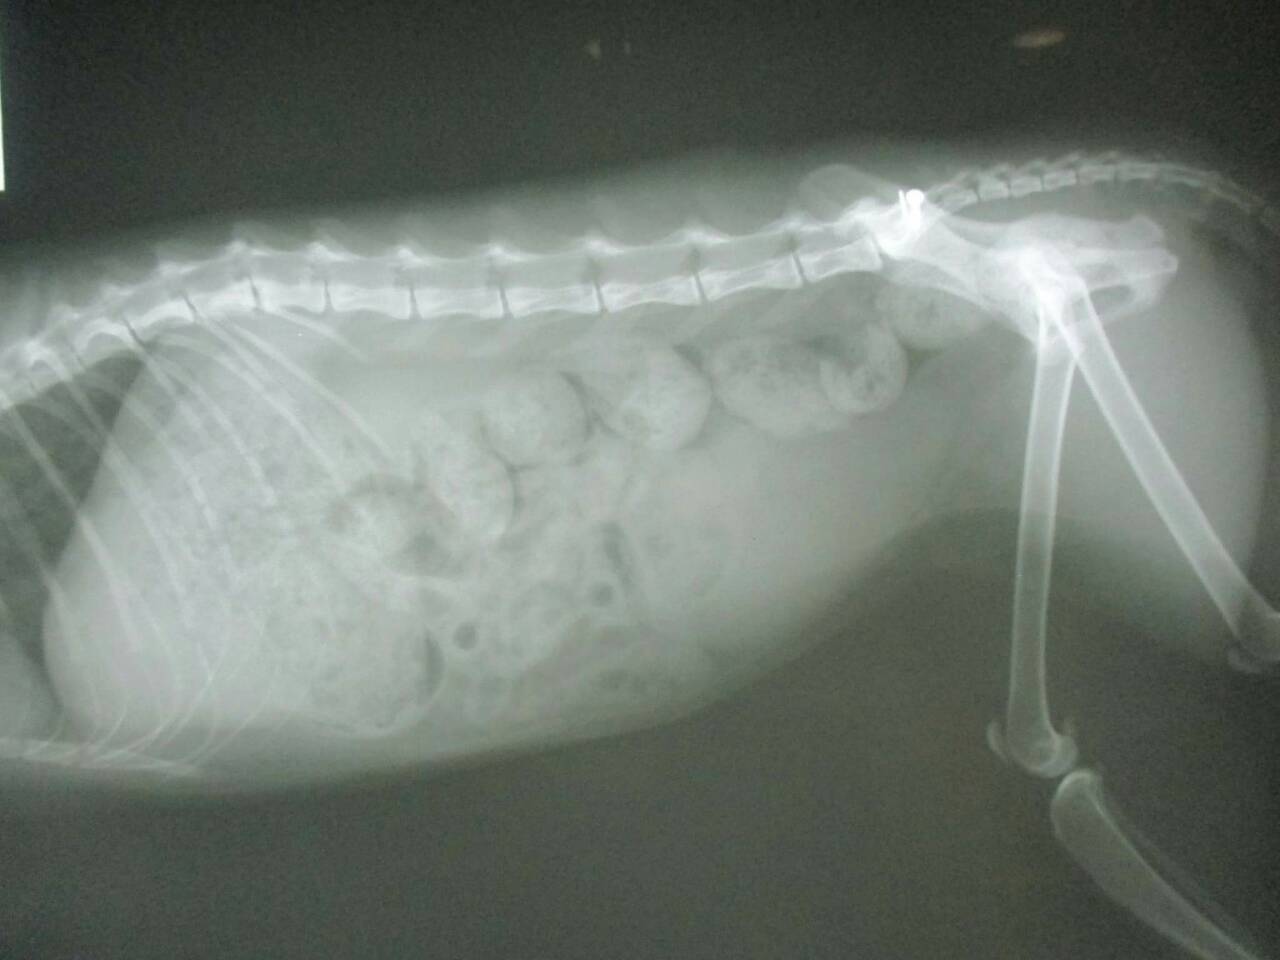

主題: 壽山收容所 背傷癱瘓貓 申請者姓名: 劉素鳳 花色: 申請日期: 2016-02-02 23:46:43 申請者部落格: 申請者臉書網址: https://m.facebook.com/sufeng.liu?ref=bookmarks 所在縣市/合作醫院: 高雄市/樂生動物醫院 治療費用: 3200元 需求人數: 8人 已結案 (2024-06-01 13:41:09) 報名人員: Freesia Tsai(已付款)、Amber Chung x2(已付款)、兔子(已付款)、karena(已付款)、Nancy Wu(已付款)、Tina Chen(已付款)、吳金英(已付款)、 候補人員: 動物病情說明: 壽山收容所專案的貓咪,這隻三花貓小刀 原本背部傷口有在癒合了,但在前一家醫院觀察後發現他後軀的神經反射有問題,後腳目前是都無法站,而且有點癱瘓的狀況,只能靠前肢撐著。

醫生初步檢查左邊腸薦關節有做手術,胸腰椎交接處(T13~L1)有受傷,可能是造成後驅癱瘓的主因,左右兩側後腳還有反射但左邊反應較差,傷口部分目前還好並無分泌物但後面幾天還是需觀察,如有分泌物出現則有可能又需做清創手術,血檢並未有異常,貓咪目前食慾還不錯,所以並未上點滴,目前會先就傷口照護為主, 醫生建議貓咪轉到大醫院做針灸的治療,努力應該會有康復的機會, 謝謝大家幫助這貓咪^^ . 、